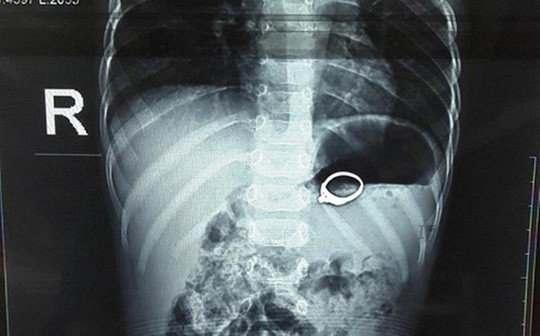

| Chiếc nhẫn nằm trong dạ dày bé 13 tháng tuổi - Ảnh: BV cung cấp |